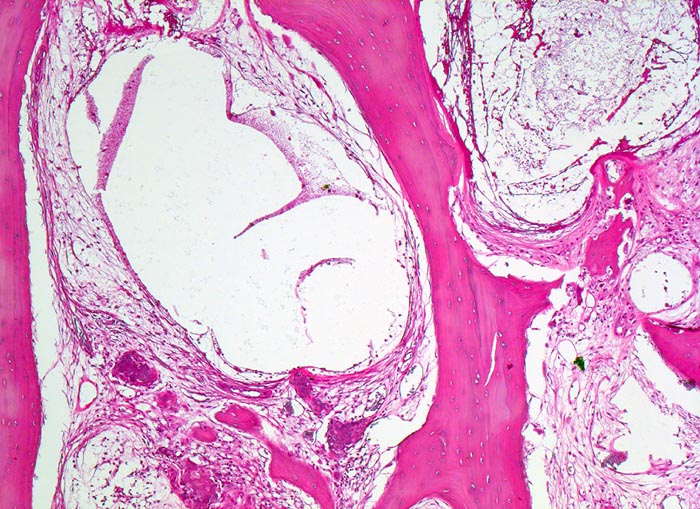

• Flächenhafte Ablösung des gut erhaltenen Gelenkknorpels zwischen subchondraler Knochenlamelle und angrenzender nekrotischer Spongiosa.

• Pseudozystische Hohlräume in den nekrotischen Markräumen.

• Fibrosiertes Mark mit einzelnen thrombosierten Arterien.